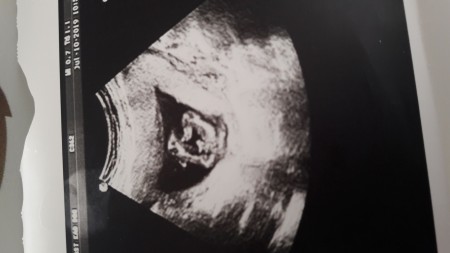

Bebeğin 15+5 bacak arası görüntüsünü paylaşcagım cinsiyet tahmini yaparmısınız . Doktor erkek oldugunu söyledi fakat ordaki bana sanki göbek kordonu gibi gözüküyor. Sizce nedir? Yan çevirip bakarmısınız.

hayir cnm erkek o erkek :) ayni sekilde benim pasaninda var rsmi

Evet kesinleşti erkek oldugu ☺